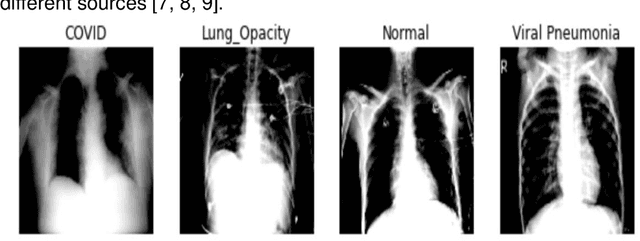

Abstract:In medical practice, the contribution of information technology can be considerable. Most of these practices include the images that medical assistance uses to identify different pathologies of the human body. One of them is X-ray images which cover much of our work in this paper. Chest x-rays have played an important role in Covid 19 identification and diagnosis. The Covid 19 virus has been declared a global pandemic since 2020 after the first case found in Wuhan China in December 2019. Our goal in this project is to be able to classify different chest X-ray images containing Covid 19, viral pneumonia, lung opacity and normal images. We used CNN architecture and different pre-trained models. The best result is obtained by the use of the ResNet 18 architecture with 94.1% accuracy. We also note that The GPU execution time is optimal in the case of AlexNet but what requires our attention is that the pretrained models converge much faster than the CNN. The time saving is very considerable. With these results not only will solve the diagnosis time for patients, but will provide an interesting tool for practitioners, thus helping them in times of strong pandemic in particular.